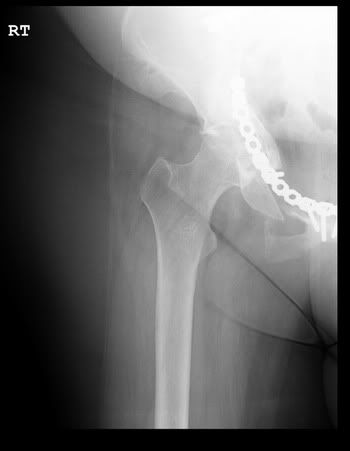

Most people don't understand why I am the way I am. I hope these x-rays give them a better idea of what I have to deal with every single day.

My hip and pelvis